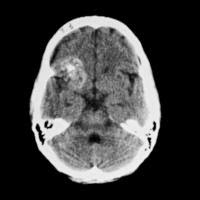

Se presenta con anillo de tejido iso o hiperdenso, típica mente de espesor uniforme

baja atenuación central (fluido / pus) y baja densidad circundante (edema vasogénico)

| Varón de 26 años con crisis epiléptica. TC: lesión hipodensa en ganglios basales con efecto masa sobre sistema ventricular en la imagen derecha, con contraste, lpresenta realce en anillo. Se solicita VIH que resulta positivo, por lo que se diagnostica de absceso por Toxoplasma. M. L. Parra Gordo, otros Guía rápida de diagnóstico de lesiones cerebrales en TC craneal de urgencias. Seram2012 |